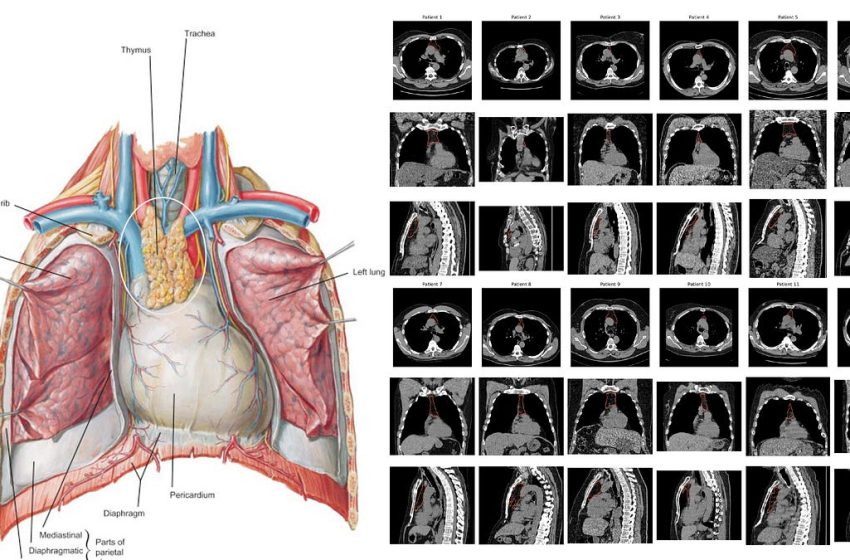

Our thymus gland plays a central role in the development of our immune system, specifically for supporting T cell development (how these cells got their name, maturation and differentiation in the thymus) and discriminating between self and foreign, non-self antigen proteins with production of dendritic cells. As we age, our thymus gland shrinks—the process known as involution—with progressive change from spongy to fatty tissue, with loss of functionality. But this process, with respect to timeline and extent, markedly varies from one person to the next. And to make things even more complicated, our thymus gland anatomy and precise location in the chest also is highly variable. So the famous Frank Netter diagrams from the 1960s (such as at left below) don’t capture the remarkable heterogeneity that a random set of 12 chest CT scans (below at right).